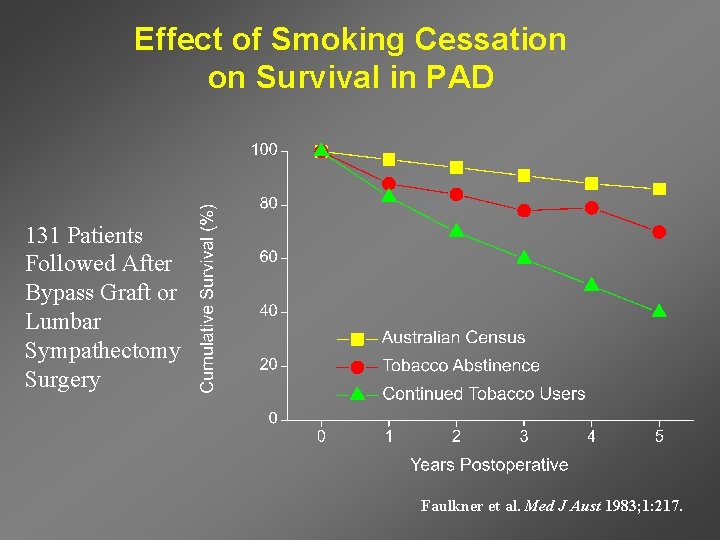

Effect of Smoking Cessation on Survival in PAD 131 Patients Followed After Bypass Graft or Lumbar Sympathectomy Surgery Faulkner et al. Med J Aust 1983; 1: 217.